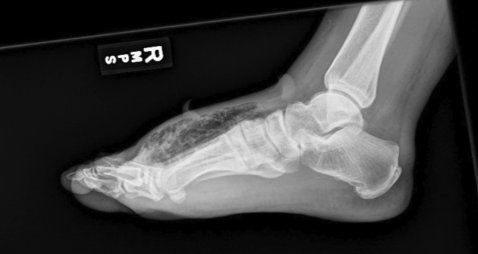

The below XR was obtained in the ED too, by the way, and read the next day by radiology as concerning for gas.

History and exam may demonstrate pain out of proportion, rapidly progressive cellulitic changes, dark discoloration or bullae, crepitus, systemic symptoms such as fever or N/V/D, and immunosuppression. That said, many of these findings may be absent or occur late. Consider imaging to look for gas, which would increase your pre-test probability. US, XR, and CT can be used. On US, gas typically appears as a bright (hyperechoic) area with shadowing beneath it. While this has low sensitivity and does not occur with all NSTIs, it is better than XR and immediately available. CT is more sensitive and can direct surgical efforts but does take more time.